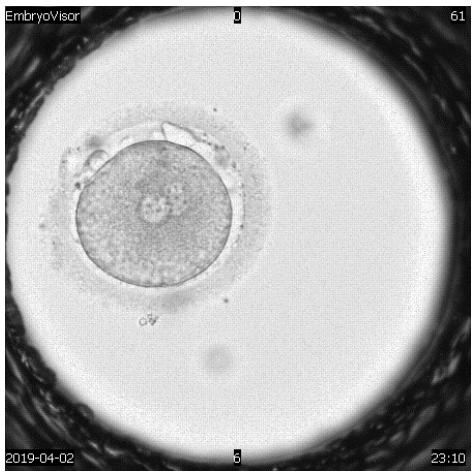

The embryological stage of ART programs is one of the most important, since the assessment of the quality of oocytes, their fertilization and in vitro cultivation to the stage of preimplantation embryos largely determines its success. Morphological evaluation of embryos is the main method of embryo selection. Time-lapse microscopy is one of the modern methods of selecting a high-quality embryo for transfer. In the analysis of many retrospective and prospective studies, they emphasize the advantage and lack of differences compared to traditional morphological assessment of the quality of embryos Almost all publications devoted to timelapse microscopy have focused on determining the timing of specific events of embryo division and then using this information to create algorithms that help to select embryo for transfer.

A detailed view of techniques used to assess human embryo development to enhance reproductive potential.